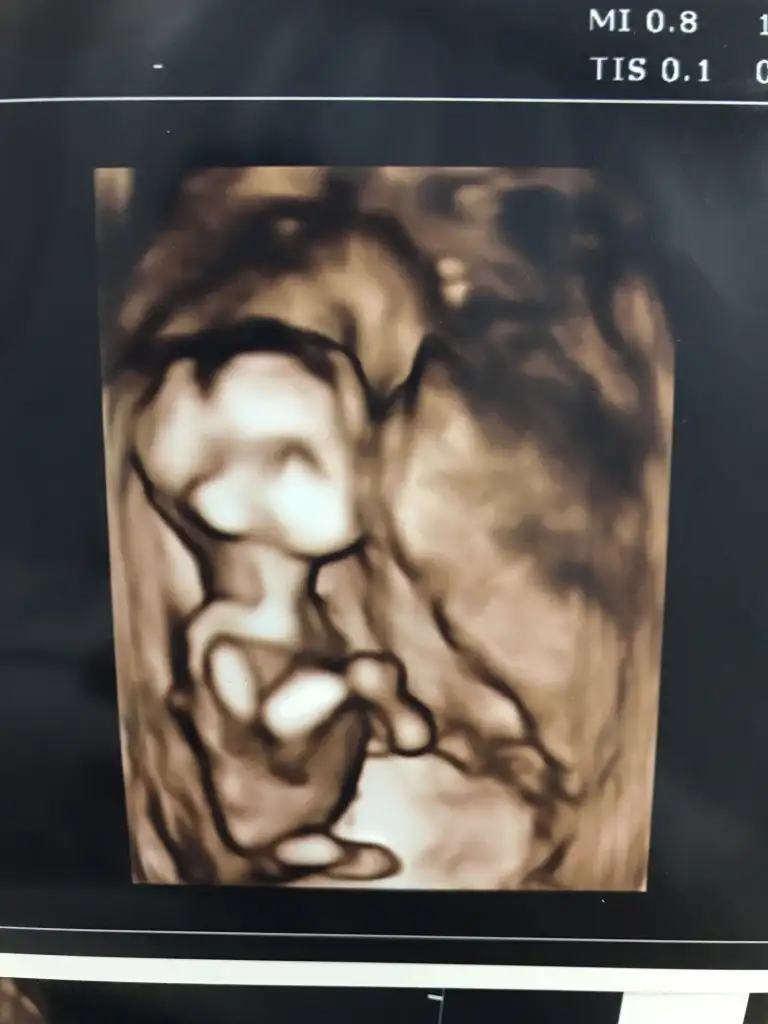

Bunlar net değilBi de bu resimler var.

Ögrendinizmi tahminim kızdışu an yanımda yok ...eve gidince bakayım o zaman..şimdiden çok teşekkürler

Evet inşaAllahTahminim dogru saglıkla gelsin